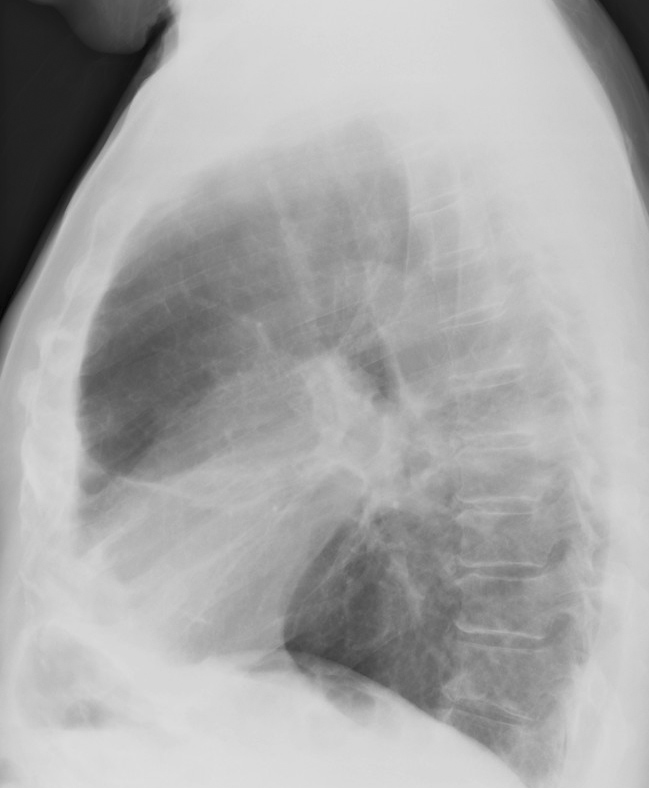

Gallery Pulmonary Fibrosis Radiation Radiation case 3

Radiation case 3